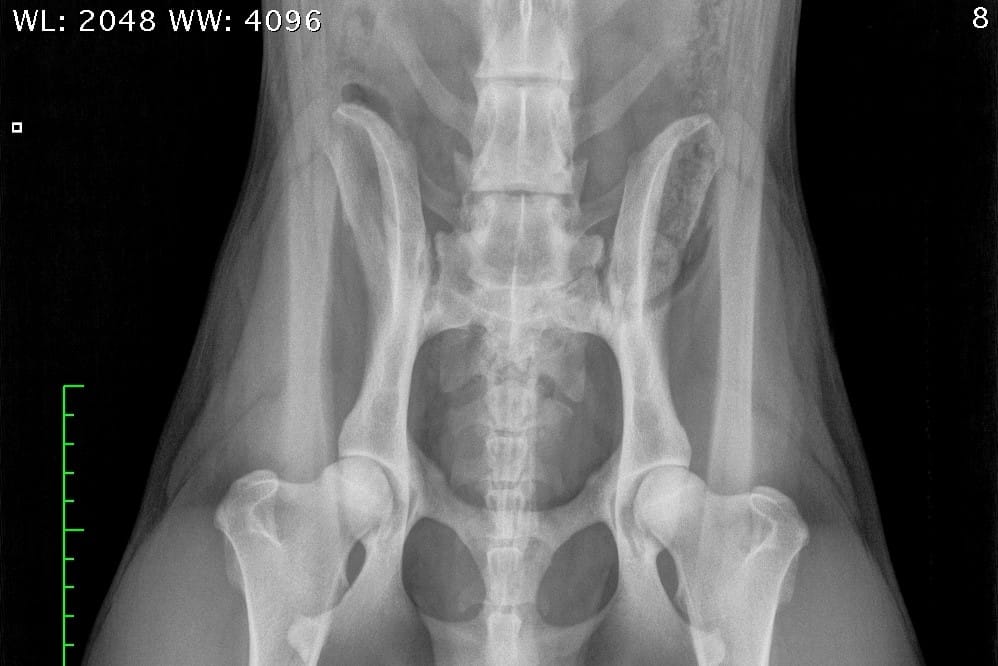

NORMAALI SELKÄRANKA

Koiran normaali selkäranka koostuu seitsemästä kaulanikamasta (C1-7), kolmestatoista rintanikamasta (T1-13), seitsemästä lannenikamasta (L1-7) ja kolmesta ristinikamasta (S1-3). Nikamien laskenta aloitetaan ensimmäisestä rintanikamasta (T1). Häntänikamien CD) määrä vaihtelee.

Ristiluu yhdistää lannerangan lantioon. Se on osa lantiota, joka sijoittuu lannerangan ja hännän väliin. Lonkkaluiden väliin asettuva ristiluu on vahva ja kolmiomainen muodoltaan. Normaali ristiluu koostuu kolmesta yhteenluutuneesta nikamasta; S1, S2 ja S3.

LTV0; normaali